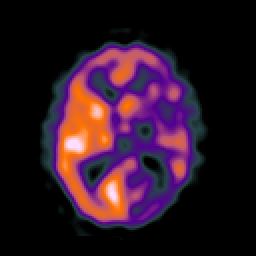

SPECT TC Study #1 -- Slice #30

[Home][Help][Clinical][Tour 1][Tour 2][Tour 3] Slice 30